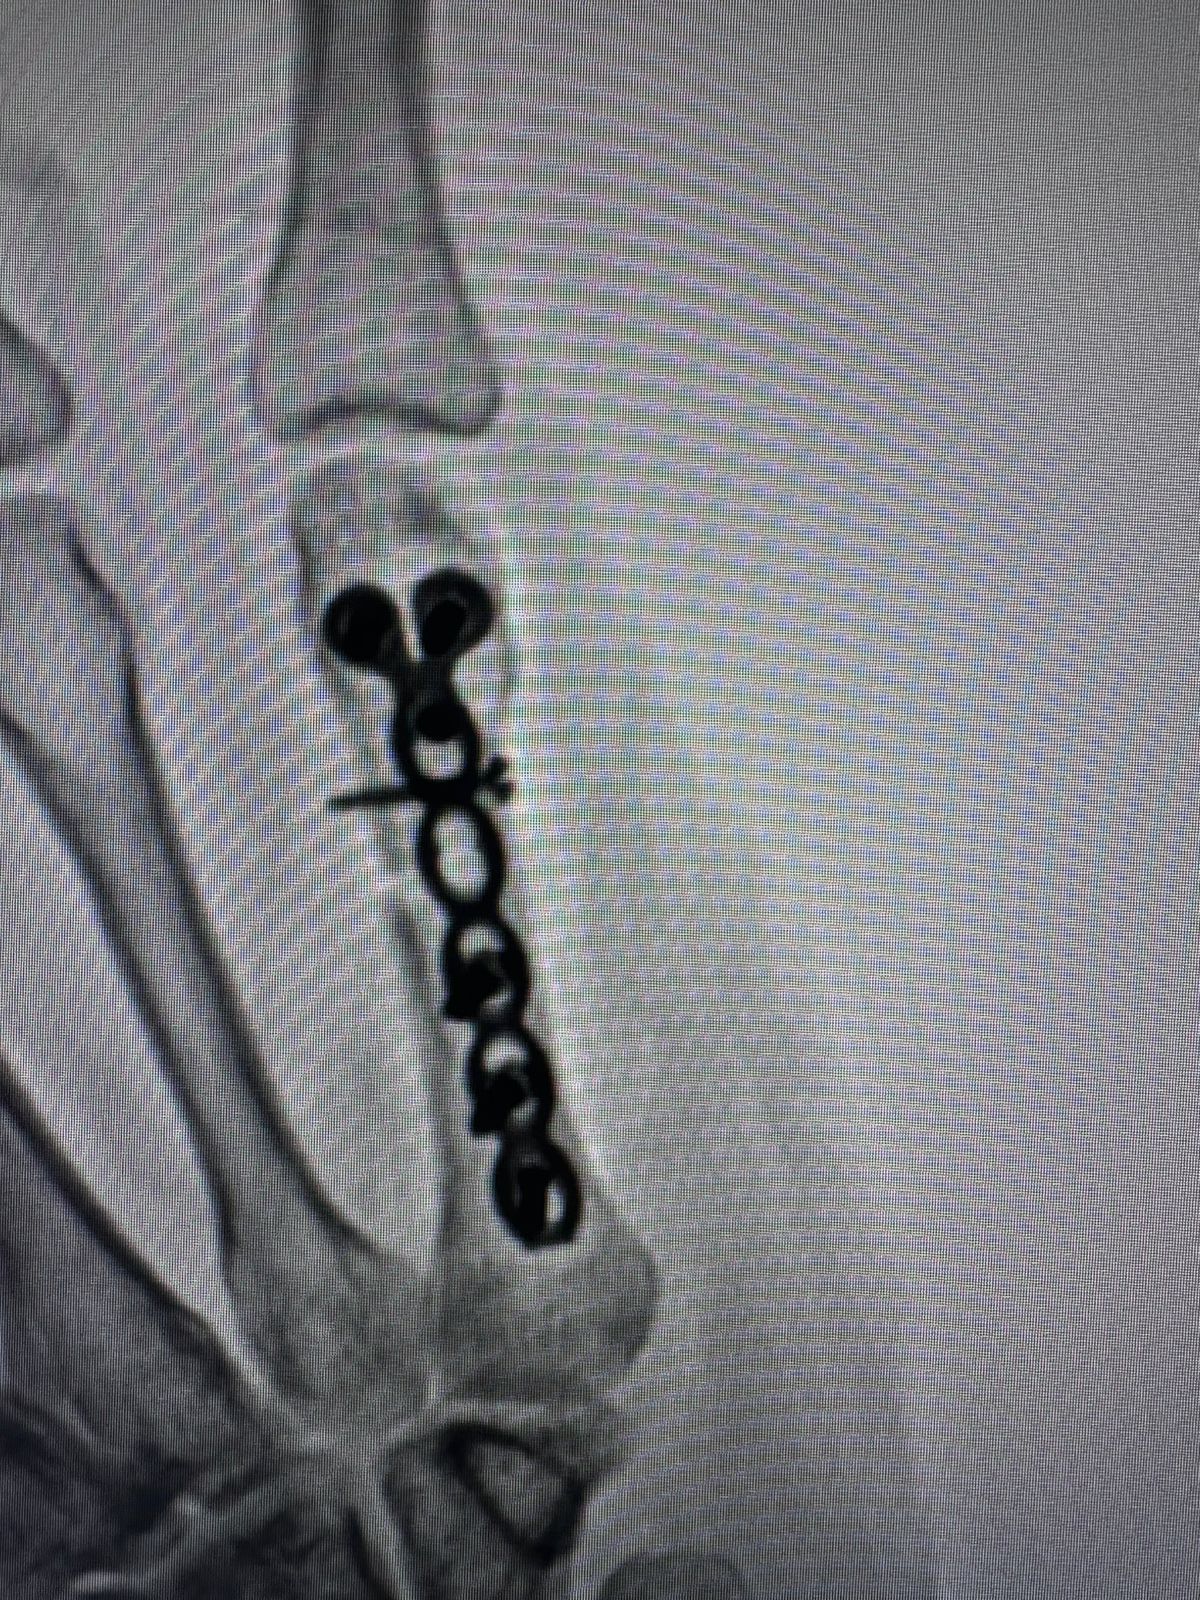

Moments That Mark Meaningful Recovery

Witness real patient transformations at The Ortho Clinic through images that reflect successful treatments and restored mobility.